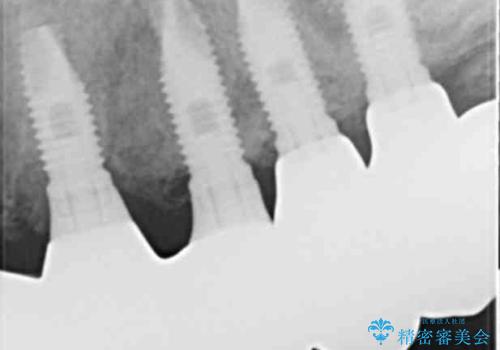

治療途中で患者様が喫煙を再開され、最もタバコの影響を受けやすい上顎前歯部(右上31)インプラント周囲の骨吸収と少量の排膿を認めました。

長期的予後不良と判断した右上3フィクスチャーを除去し、人工骨による骨増生及び右上2に埋入を行いました。

保存可能な右上1のフィクスチャーは粘膜下にスリープさせ、左上2の埋入を行いました。

当初は上顎③2①12③ブリッジの予定でしたが、リカバリー手術後上顎3②11②③ブリッジによる補綴を行いました。